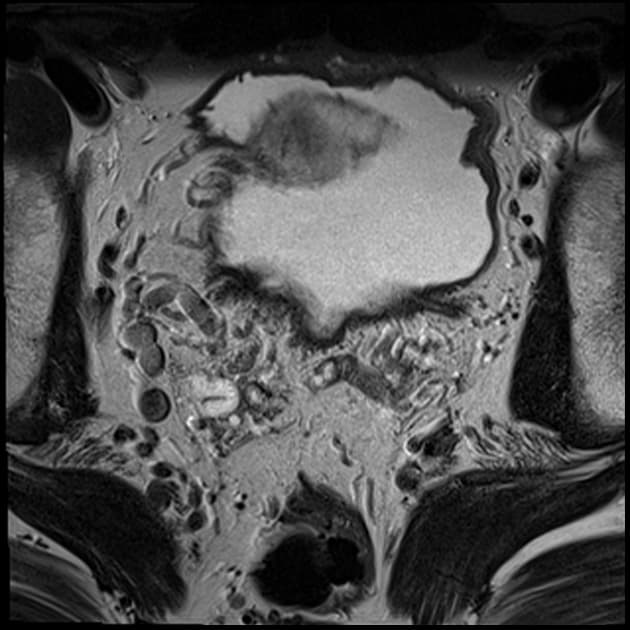

Axial T2

MRI•Axial T2•1 Img

Ca bệnhUng thư tuyến tiền liệt - nốt vùng đỉnh PI-RADS 3

Ung thư tuyến tiền liệt - nốt vùng đỉnh PI-RADS 3

Chụp cộng hưởng từ đa tham số (mp MRI) tuyến tiền liệt (prostate)

- MRI đa mặt phẳng (multiplanar MRI) cho thấy một nốt vùng đỉnh phía trước (anterior apical nodule) thuộc vùng chuyển tiếp (transition zone), giới hạn không rõ (ill-defined), có hạn chế khuếch tán (restricted diffusion) và ngấm thuốc sớm mạnh (early avid enhancement).

Ung thư tuyến tiền liệt (Prostate cancer) - nốt vùng đỉnh (apical nodule) PI-RADS 3